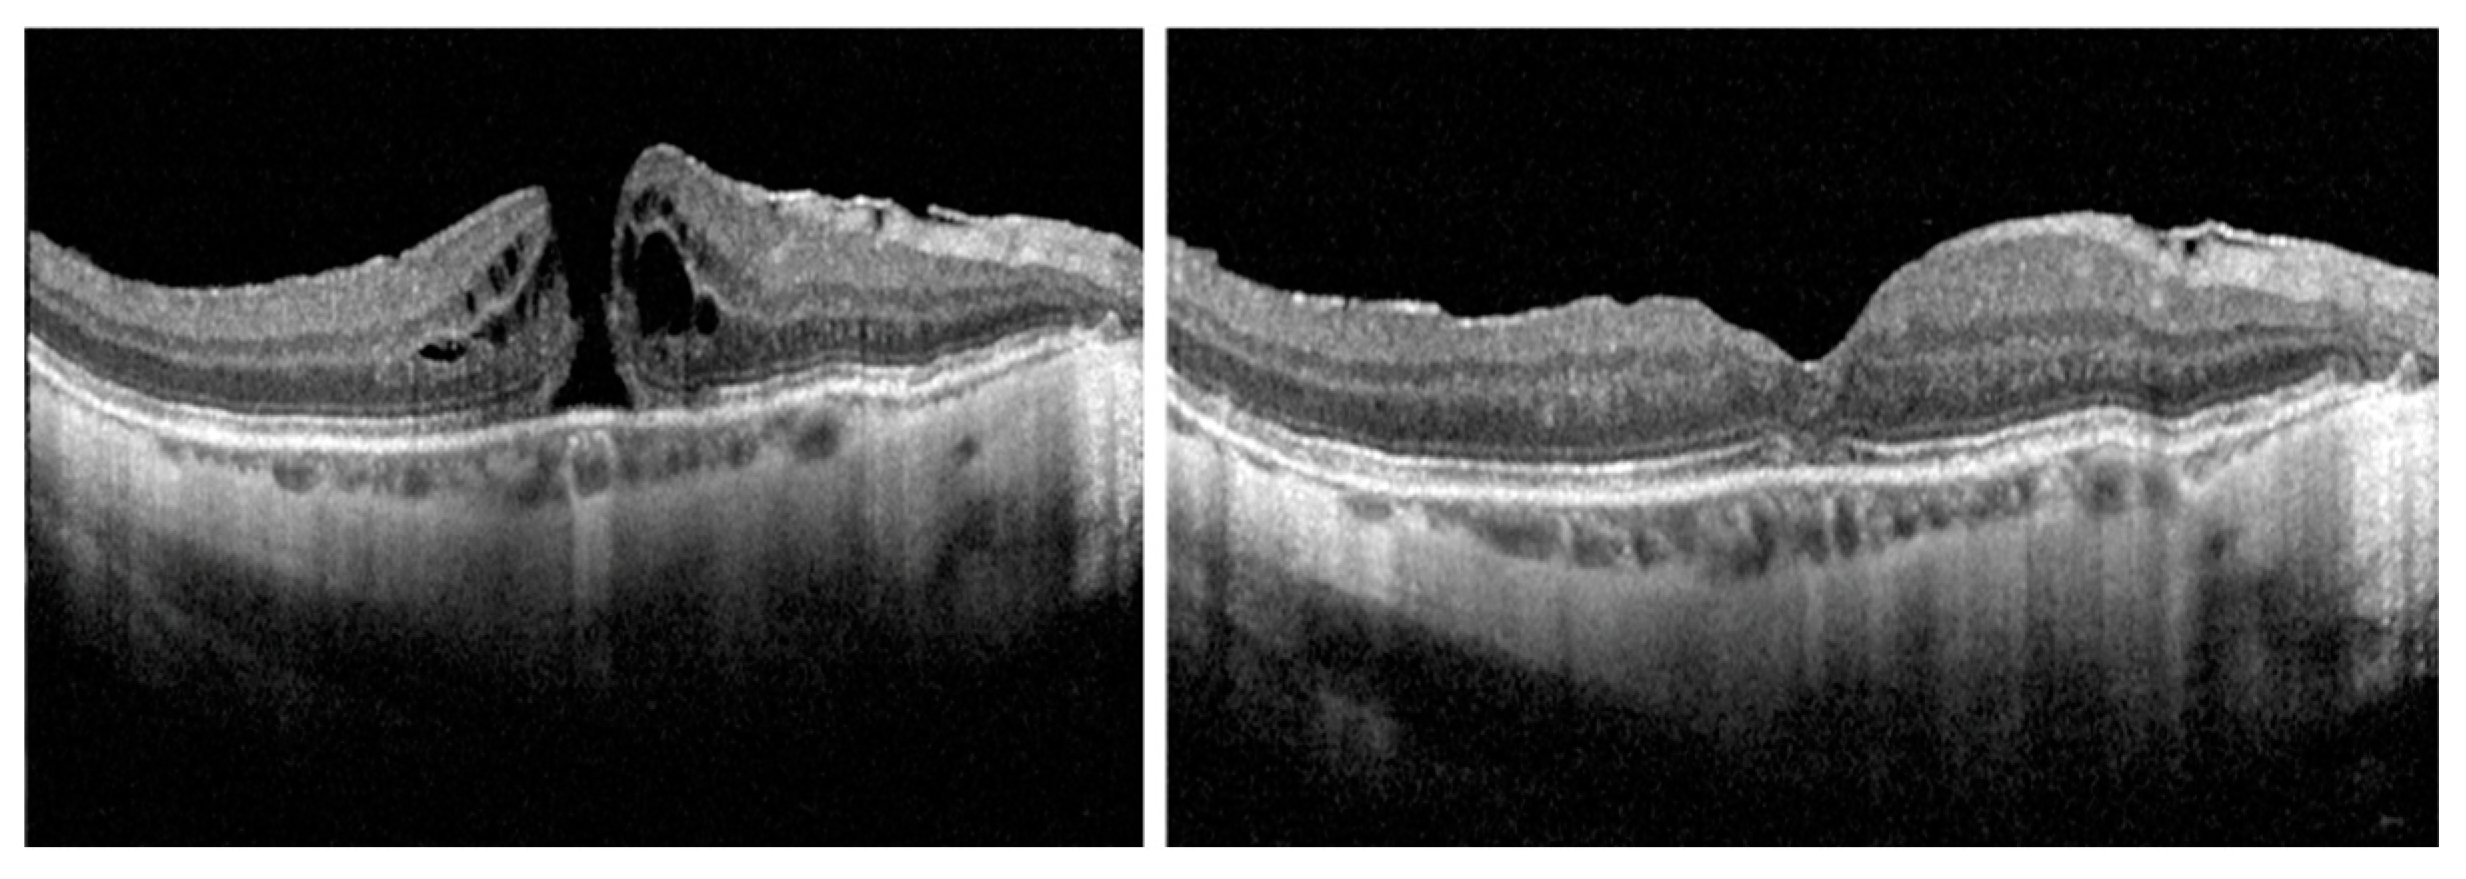

| Closure rate | 26/28 (92.9%) | 11/12 (91.7%) | 11/12 (91.7%) | 4/4 (100%) |

| Closure type 1A | 13/28 (46.4%) | 5/12 (41.7%) | 5/12 (41.7%) | 3/4 (75.0%) |

| Closure type 1B | 2/28 (7.1%) | 1/12 (8.3%) | 0/12 (0%) | 1/4 (25.0%) |

| Closure type 1C | 11/28 (39.3%) | 5/12 (41.7%) | 6/12 (50.0%) | 0/4 (0%) |

| Residual ELM defect | 8/28 (25.6%) | 6/12 (50.0%) | 4/12 (33.3%) | 1/4 (25%) |

| Residual EZ defect | 21/28 (75.0%) | 8/12 (66.7%) | 11/12 (91.7%) | 2/4 (50%) |

| Fibrin-like HR tissue | 1/28 (3.6%) | 1/12 (8.3%) | 0/12 (0%) | 0/4 (0%) |